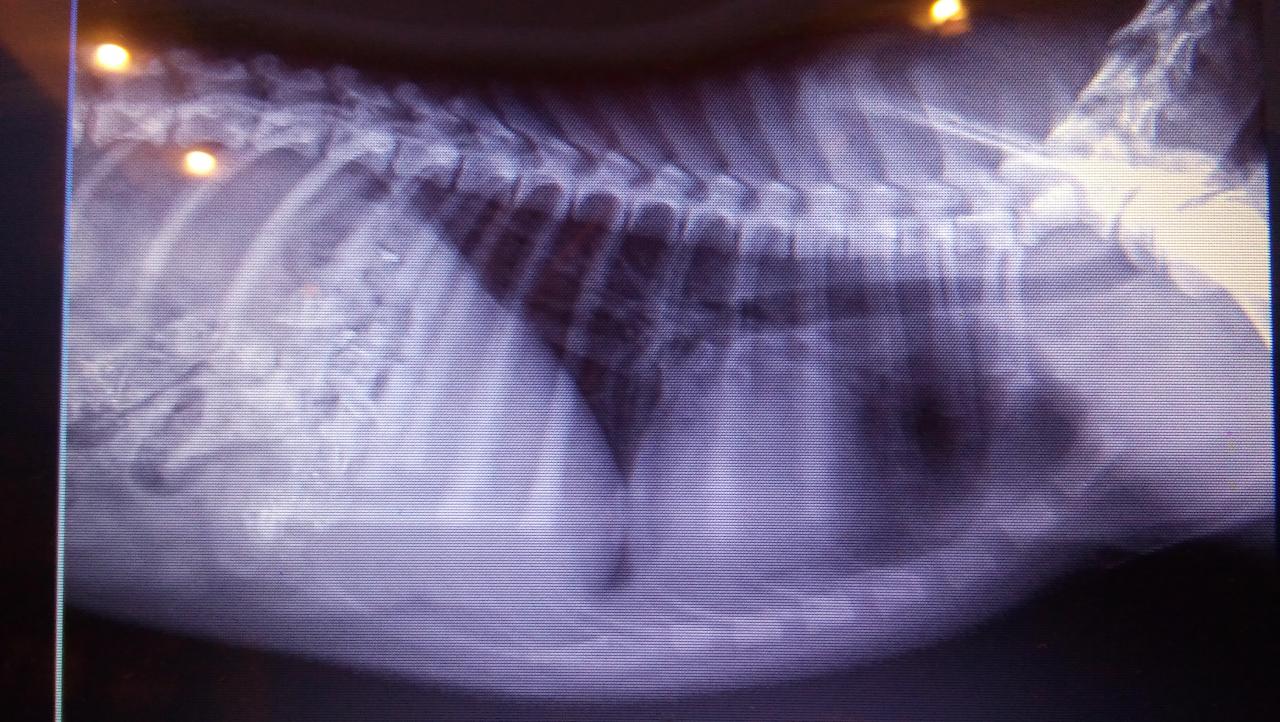

Позавчера днем собака, девочка 6 месяцев была сбита машиной ОДЕССА, ул. Невского. Перелом таза, перелом подвздошной кости. Вертлюжной впадины, седалищной кости, смещение по кресцовому сочленению, травма мочевого пузыря. Первая помощь оказана, но необходима срочная операция. огромная просьба всех неравнодушных оказать материальную помощь. На операцию предположительно надо 6000 гр. можно в клинику vita ОДЕССА , можно на карту привата - 5168757371721533. Куратор Светлана. 0969806055